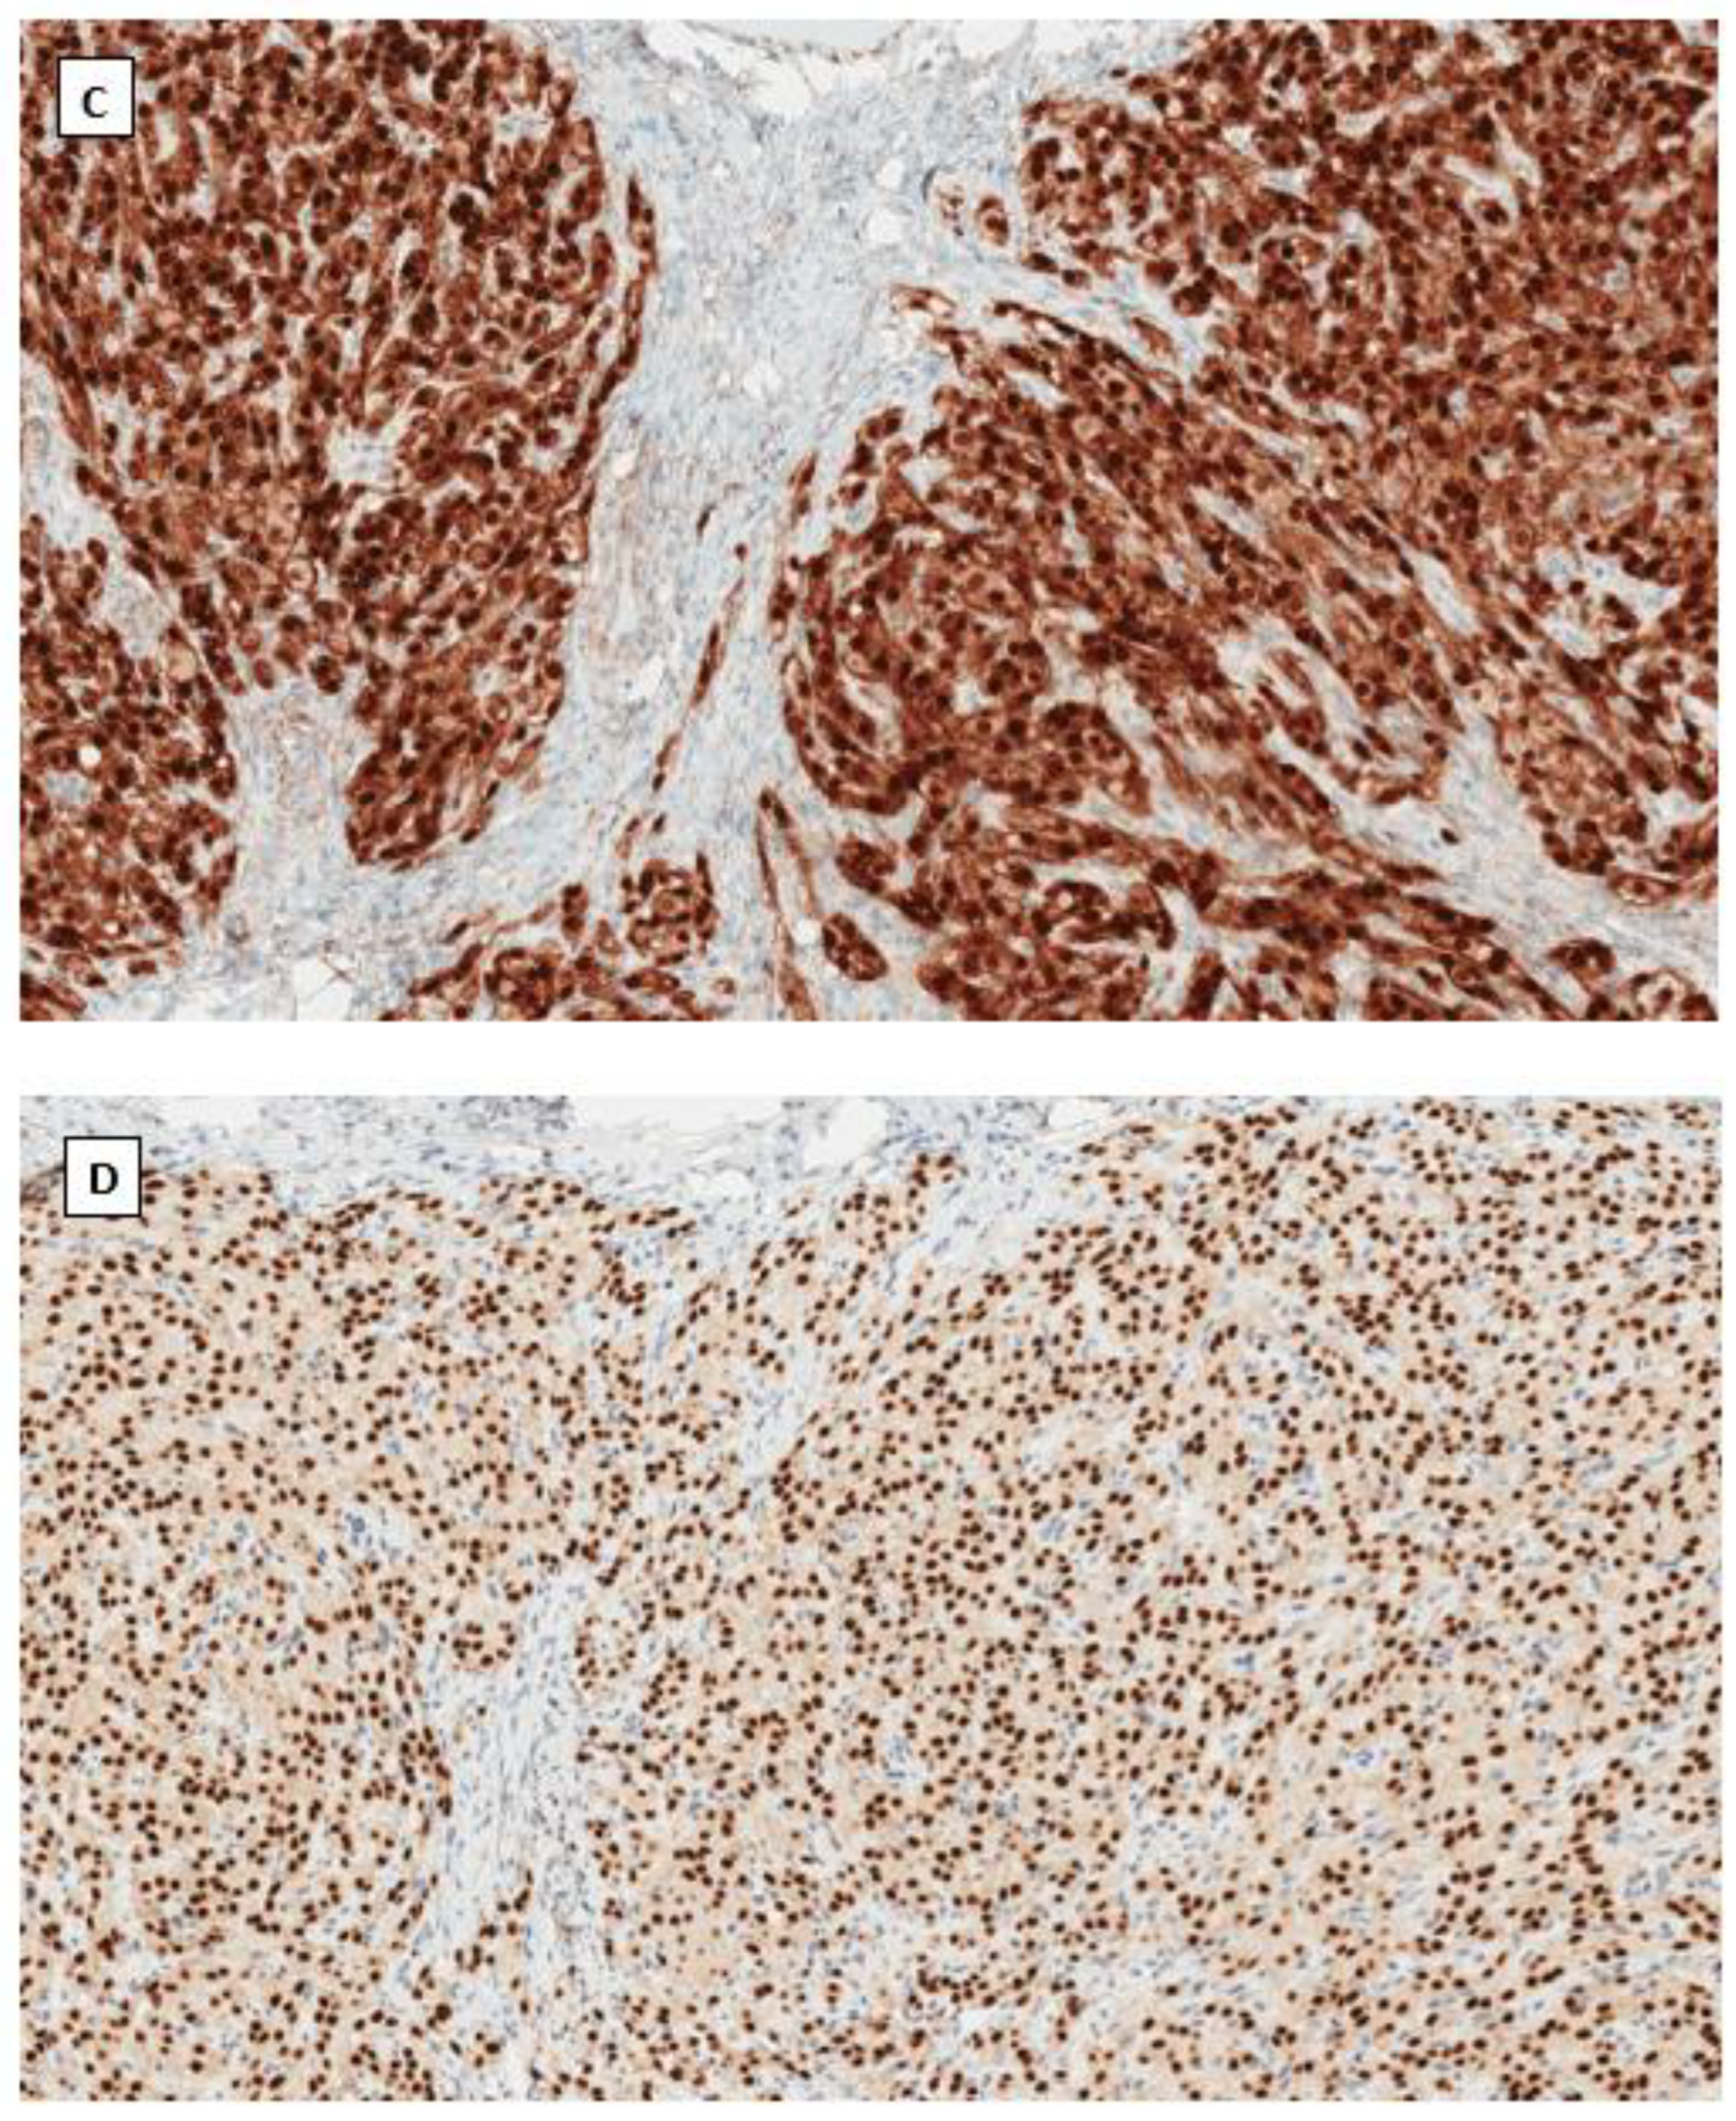

4.3. Signet Ring Stromal Cell Tumor (SRSCT)

4.4. Immunohistochemical Phenotype Shared in Ovarian Low-Grade Stromal Tumors